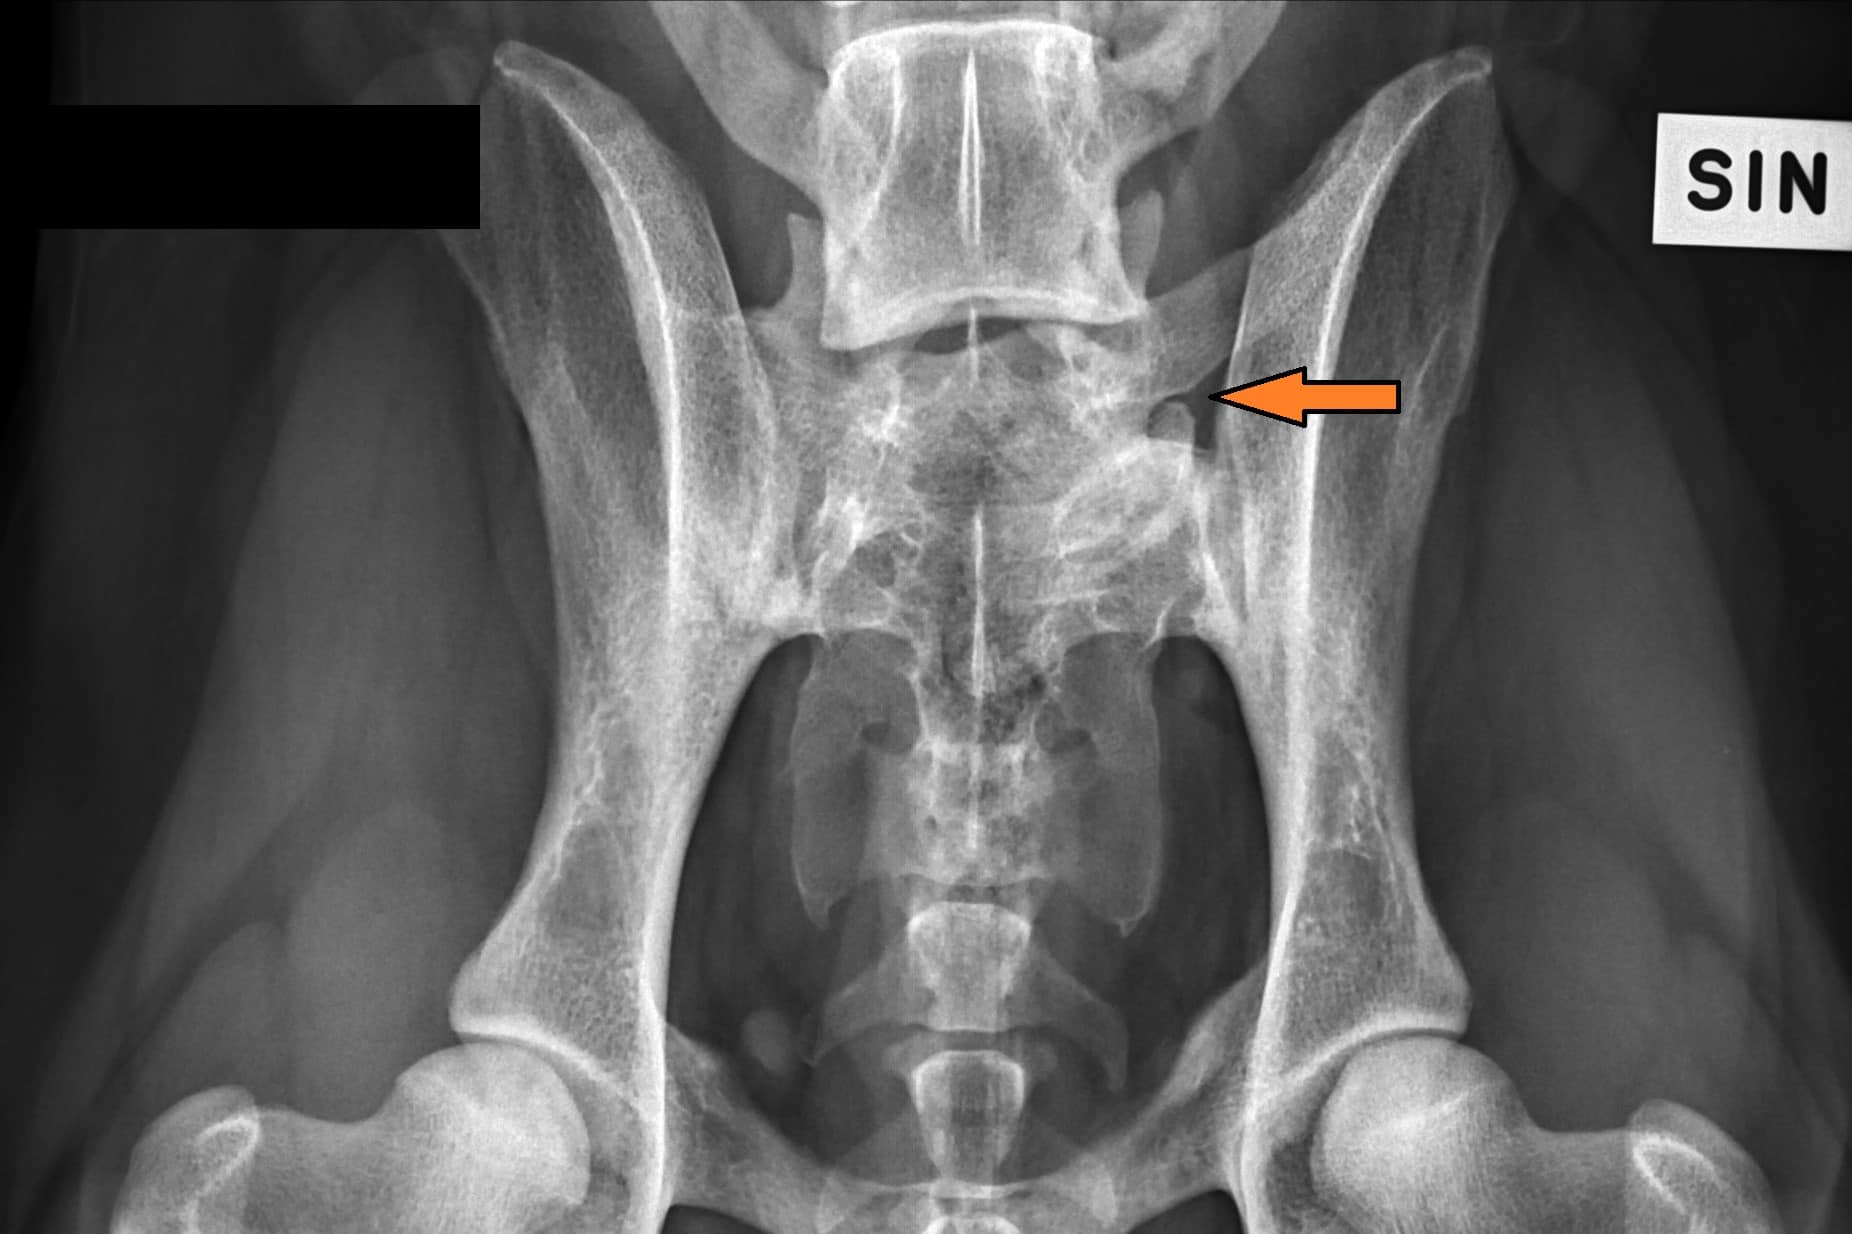

Lumbosacral transitional vertebra (LTV) in Rhodesian Ridgebacks

LTV3_VD_ARR-3

LTV2_VD_ARR-1